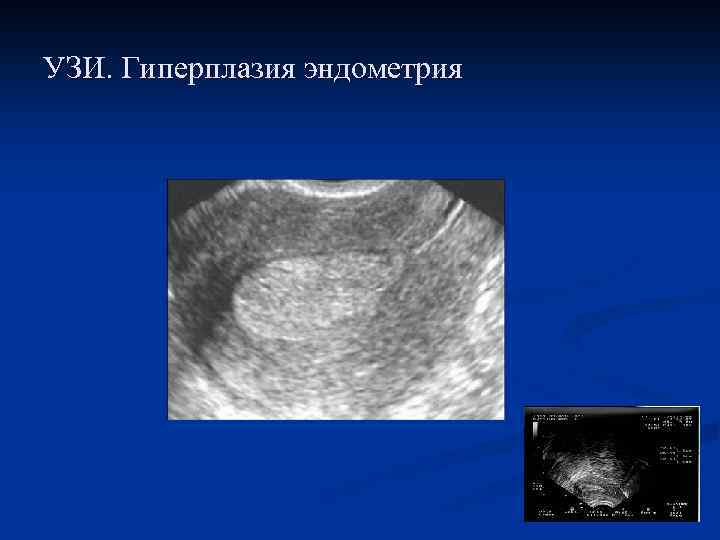

Железистая гиперплазия эндометрия (типичная) n часто определяется у больных с ановуляторными ДМК n при УЗИ – утолщенный неоднородный эндометрий n при выскабливании полости матки –обильный соскоб n при макроскопическом исследовании удаленной матки утолщенный до 1 – 2 см эндометрий n при гистологическом исследовании: повышение количества элементов стромы, желез, с некоторым преобладанием желез. Железы различной формы, могут быть кистовидно расширенные железы, железы выстланы высокопризматическим эпителием, встречаются фигуры митоза n малигнизация встречается в 0, 4 - 1 %

УЗИ. Гиперплазия эндометрия